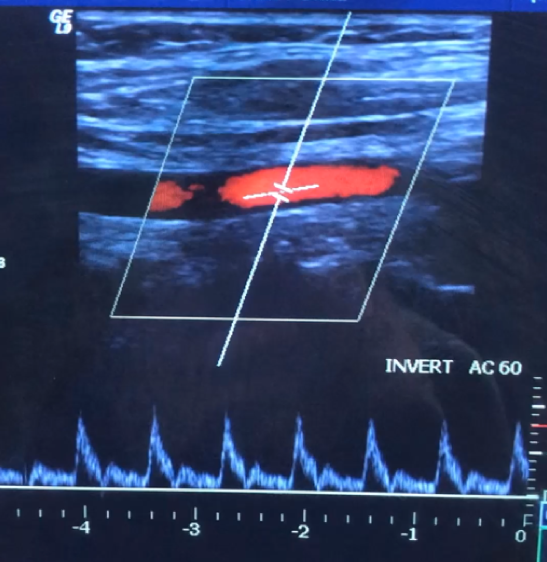

What Doppler feature is demonstrated in the spectral waveform?

Spectral broadening indicating disturbed/turbulent flow

Based on the Doppler image, which finding best characterizes the hemodynamics at the sampled site?

Focal flow acceleration with spectral broadening consistent with a stenotic jet

Which combination of Doppler findings most strongly supports hemodynamically significant stenosis in this image?

Elevated peak velocities with spectral broadening and evidence of flow disturbance

The Doppler sample volume in this image is most likely located:

Distal to a stenosis

Identify TWO abnormal Doppler findings present in this image.

Spectral broadening + turbulent/chaotic flow with eddy currents